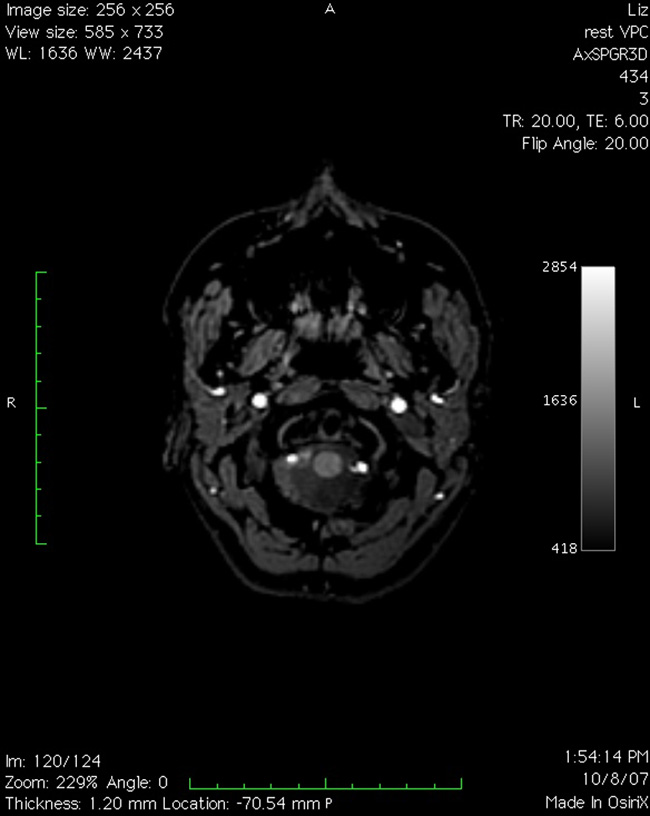

TERRENOS ESCANEADOS/fMRI on an Affordaplane surface

. Basement installation (entry from N.Hancock Street, Richmond, VA); initiated by a neuroimaging experiment. 2008.